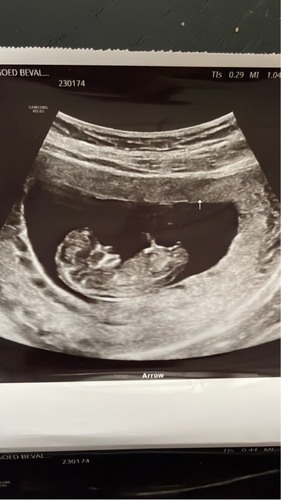

Echo is gemaakt met 11+1 dus nog een beetje vroeg maar toch! Meisje he?🫣

Ik kan geen nubs lezen, maar tot 12 weken staat ie sowieso in meisjesstand dus dan kan je er niks van maken. Pas vanaf 12 weken kan de nub veranderen in een jongensstand.

Ik denk ook meisje